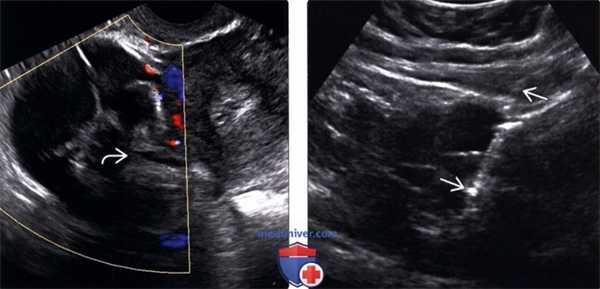

(Левый) На трансвагинальном УЗ срезе с цветовой допплерографией у этой же пациентки лучше визуализируется солидные компоненты с неровными контурами в сложном кистозном образовании со слабым допплерографическим сигналом.

(Правый) Изображение, полученное при тонкоигольной аспирационной биопсии под УЗ контролем; визуализируется игла в наиболее неоднородном солидном очаге. При цитологии выявлены клетки рака ободочной кишки. Чрескожная биопсия обычно не используется для диагностики подозрительных новообразований яичников, но требуется в случае подозрения на метастатическую болезнь.